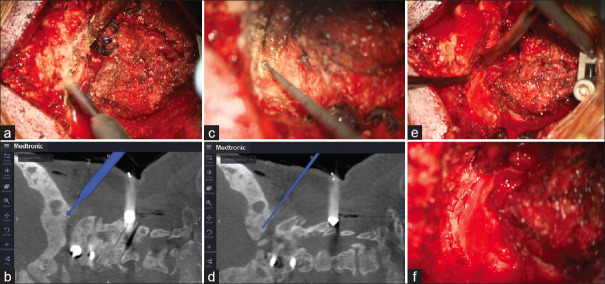

纤维发育不良(FD)是一种罕见的骨骼疾病,其特点是正常骨骼被纤维结缔组织取代,导致骨骼形成异常。本病例报告详细介绍了一名颅椎骨交界处纤维发育不良的 61 岁女性患者的成功治疗过程。该患者曾有颅内脑膜瘤病史,并已被诊断为 FD,在一次跌倒后出现步态障碍和肌肉无力。影像学检查显示,患者的颅骨和颈椎有广泛的多发性 FD 病变,C2 骨突骨折导致脊髓受压。患者接受了枕颈固定和减压手术。术中使用了 O 型臂导航,以确保准确放置螺钉和有效减压。该手术可以正确定位C2和C3椎弓根螺钉、切除增生的枕骨和C1后弓、放置枕骨钢板并避开囊肿组件。在两年的随访中,没有发现螺钉松动的迹象,患者的临床症状明显改善。该病例强调了量身定制的手术策略和先进导航技术在处理复杂 FD 病例,尤其是涉及 CVJ 的病例中的重要性。它还凸显了治疗多发性 FD 所面临的挑战,因为完全切除往往是不可行的。该病例的成功结果支持使用减压手术结合稳定术来缓解症状并预防进一步的并发症。

Fibrous dysplasia (FD) is a rare skeletal disorder characterized by the replacement of normal bone with fibrous connective tissue, leading to abnormal bone formation. This case report details the successful treatment of a 61-year-old woman with FD at the craniovertebral junction (CVJ). The patient, who had a history of intracranial meningioma and had already been diagnosed with FD, experienced worsening gait disturbance and muscle weakness following a fall. Imaging studies revealed extensive polyostotic FD lesions in the skull and cervical spine, along with a C2 odontoid fracture causing spinal cord compression. The patient underwent occipitocervical fixation and decompression surgery. Intraoperative O-arm navigation was used to ensure accurate screw placement and effective decompression. This procedure allowed for proper positioning of the C2 and C3 pedicle screws, resection of the hyperplastic occipital bone and C1 posterior arch, and placement of the occipital plate with avoiding the cyst components. At a 2-year follow-up, there were no signs of screw loosening, and the patient showed marked clinical improvement. This case emphasizes the importance of tailored surgical strategies and the use of advanced navigational technologies in managing complex FD cases, particularly those involving the CVJ. It also highlights the challenges of treating polyostotic FD, where complete resection is often unfeasible. The successful outcome in this case supports the use of decompressive surgery combined with stabilization to relieve symptoms and prevent further complications.